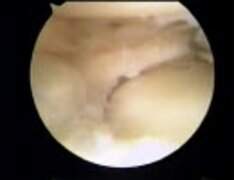

膝半月板内視鏡手術